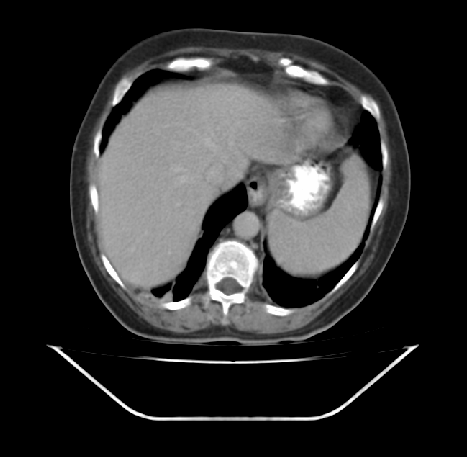

ist jemand unter Euch der sich auskennt mit CT Aufnahmen ?

Ich habe 3 Stück angehangen, sie stammen aus einem CT der Abdomen.

Möglich das es eine Serie eines Querschnitts darstellt Bild 1 zeigt den Start,Bild 2 eines aus den mittleren Aufnahmnen und Bild 3 das letzte dieser CT Serie.

Da ganz gezielt auf ein und die gleiche Stelle gehalten wurde mit sagenhaften über 80 Einzelaufnahmen interessiert mich brennend um die Darstellung welches Organges es sich bei diesen Aufnahmen handelt und ob darauf etwas bedenkliches eingekreist wurde.

Dazu fielen mir dann eben diese Aufnahmen im Nachhinein in die Hände bei denen ich stutzig wurde, da sie ja offenbar ein Organ darstellen....eine PLL aber doch eher im Blut abläuft und nicht direkt an Organen, ein Befund vom Zeitraum der Diagnosestellung eines dritt Arztes den sie hinzu zog der sie beruhigte nach Blutkontrollen es sei keine PLL sondern eine vorrübergehende Leukozytose durch eine Nierenentzündung und das seltsame Verhalten und der Ablauf dort zum Ende, wo mir noch einen Tag zuvor versichert wurde auf direktes fragen ob man dies befürchten müsse "Nein keinesfalls in den nächsten 12 Monaten, definitiv nicht".